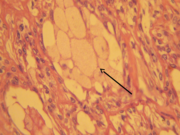

Nidos tumorales de estructura tubular separados por septos hialinos acidófilos (flecha gruesa) y revestidos por células luminales y adluminales (flecha fina). Coloración H/E.